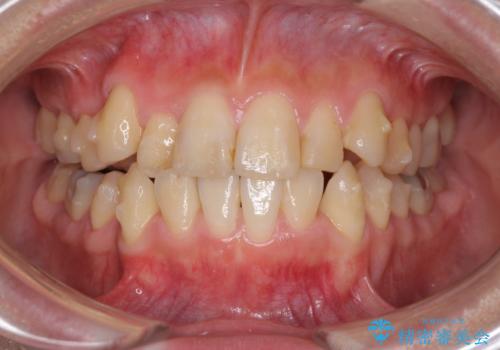

- 上下の八重歯を気にして来院された患者様です。

八重歯の後ろの歯を1歯抜歯し、補助装置(リンガルアーチ)を用いて八重歯の位置を改善し、その後インビザラインにより矯正治療を行うこととしました。